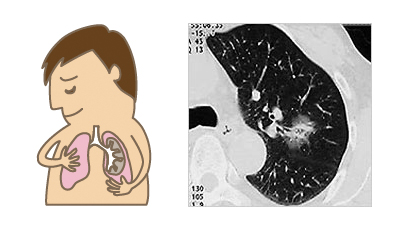

呼吸器内科、放射線科、リハビリテーション科との連携を保ちながら、術前から術後までより包括的な診療を行うように心がけています。

- 肺癌手術では23年度(呼吸器外科・鷲尾赴任時)から、より低侵襲な術式である 完全胸腔鏡下手術(Complete VATS;以下cVATS)を導入しています。肺葉切除だけではなく、より高度な技術が必要とされる区域切除・亜区域切除にも対応しており当科での基本術式としております。

肺癌手術の低侵襲化と当科での取り組み

以前は肺癌の手術といえば、胸を横切るように、約20cmから30cm切って、広背筋、前鋸筋、肋間筋等の呼吸に必要な筋肉を切離し、肋骨を1~2本切断して手術を行っていました。ここ数年来胸腔鏡というカメラを胸腔内に挿入し、その画像をモニターで見ながら手術を行うVATSと呼ばれる手術が施行可能になってきました。VATSは大きくわけて、ハイブリッド胸腔鏡下手術(Hybrid VATS)と完全胸腔鏡下手術(Complete VATS)という二つの方法があります。その二つの大きな違いは、Hybrid VATSは胸腔鏡で映し出されたモニター画面を見たり、5~10cmの創から直接覗き込んで見たりしながら手術を行うのに対して、Complete VATSは、すべて胸腔鏡で映し出されたモニター画面をみて手術を行うという違いがありまあす。そのため創は最大のもので3cm程度ですみ、呼吸筋の切離も最小限ですみ、術後の疼痛や機能回復もさらに良好になると思われます。

肺癌は胸腔内臓器であり、胸腔内へのアプローチ法には主に以下があり侵襲の大きさもそれぞれ異なります。

- 標準開胸:

皮膚切開・呼吸筋の切離範囲も大きく、肋骨も1~2本切離する。 - Hybrid VATS:

標準開胸より皮膚切開は小さく、肋骨も切離しない事が多いが、呼吸筋の切離はかなり広い範囲で行われる。 - Complete VATS:

Hybrid VATSよりさらに皮膚切開が小さく、呼吸筋の切離範囲も極めて少ない。